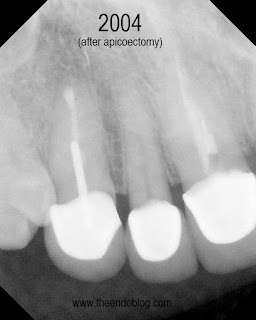

Apicoectomy completed, no root fractures seen with microscope. MTA retrofill.

9.5 year recall.  Tooth is fully functional, asymptomatic with radiographic healing.  Apicoectomy has preserved the tooth and the periodontium for an extended period of time.